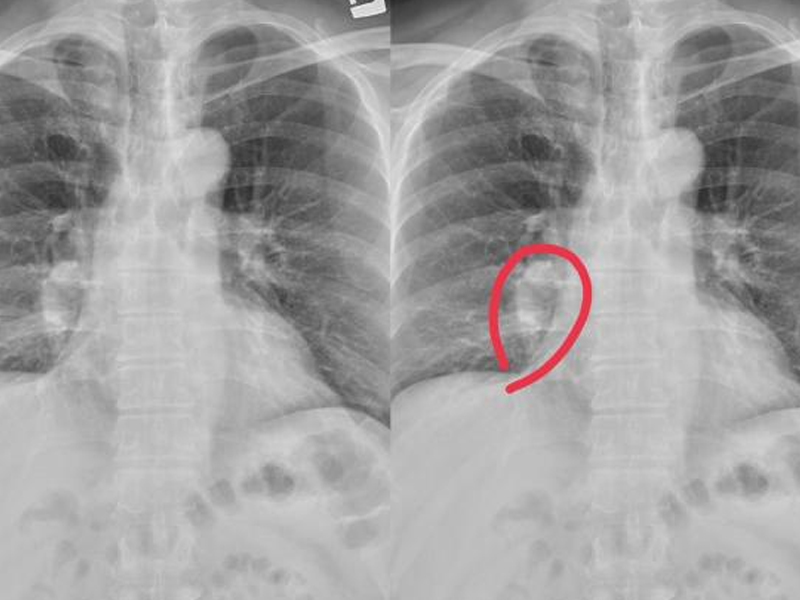

乳腺癌是常見的惡性腫瘤,而早期乳腺癌指的是病變組織處於早期狀態,即乳房腫塊小於 2 厘米,且無腋窩及遠處器官轉移。 早期乳腺癌如果及時發現,經過規範化的綜合治療,多數患者可得到治愈,能夠以良好的生存狀態長期生存。 哪些女性是早期乳腺癌高發人群? 以下 6 類女性是早期乳腺癌常見人群,建議到正規醫院甲乳外科或乳腺外科就診並諮詢處理建議: 1. 絕經前後女性:乳腺癌發病風險隨著年齡增大而升高,高發年齡為 40~54 歲。 2. 初潮年齡早、絕經年齡晚、從未生育或者生第一個孩子時年齡超過 30 歲:這部分屬於體內雌激素水平高的人群,因身體暴露於雌激素的時間增加,乳腺癌發病風險增高。 3. 有乳腺癌家族史人群:家族遺傳或基因缺陷,母親患有乳腺癌的女性發病風險明顯升高。 4. 患有乳房疾病人群:某些乳房疾病(如乳房良性腫瘤)患者風險相對普通人更高。另外,一側患有乳腺癌的女性,另一側乳房發生乳腺癌風險也升高。值得一提的是,乳腺小葉增生在低齡女性中發病率相當高,但其導致乳腺癌的概率微乎其微。 5. 肥胖、長期飲酒女性:在我國,BMI 界於 24.0~27.9 kg/㎡ 定義為超重,BMI ≥ 28 kg/㎡ 定義為肥胖,BMI 具體算法是用體重(千克)除以身高(米)的平方。飲酒等不良生活方式,會增加乳腺癌的風險。 6. 受到電離輻射的人群:乳房接受過量電離輻射治療等。 |